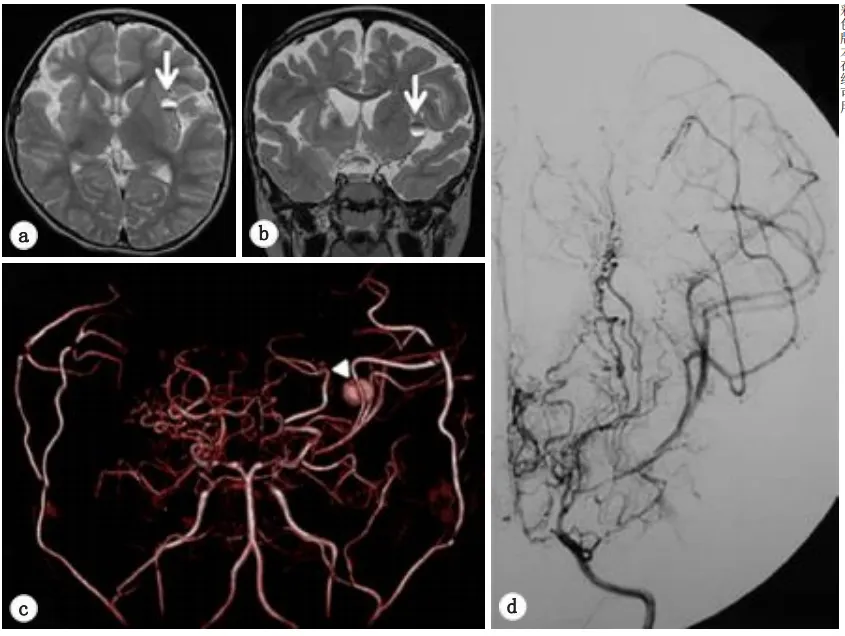

图1a:双侧CTA显示左侧颈内动脉血管严重狭窄,颈内动脉的末端前部和中部的动脉和起源可见于两侧的脑动脉,还可以看到烟雾动脉。

各种影像也证实了这一点:脑DSA显示双侧ICA末端、大脑前动脉近端和MCA严重狭窄(图1)。其他相关检查显示右侧额叶CBF明显降低,且曾经发生过脑梗死。

图3:轴向(a)和冠状(b)T2加权磁共振图像显示,左侧岛叶皮质有一个小的圆形混合强度质量(箭头)。(c)体积渲染磁共振血管造影显示,在大脑中动脉的左远端(箭头)发现一个浆果状病变,怀疑大动脉瘤。(d)左侧颈内动脉造影术未发现动脉瘤等异常表现。